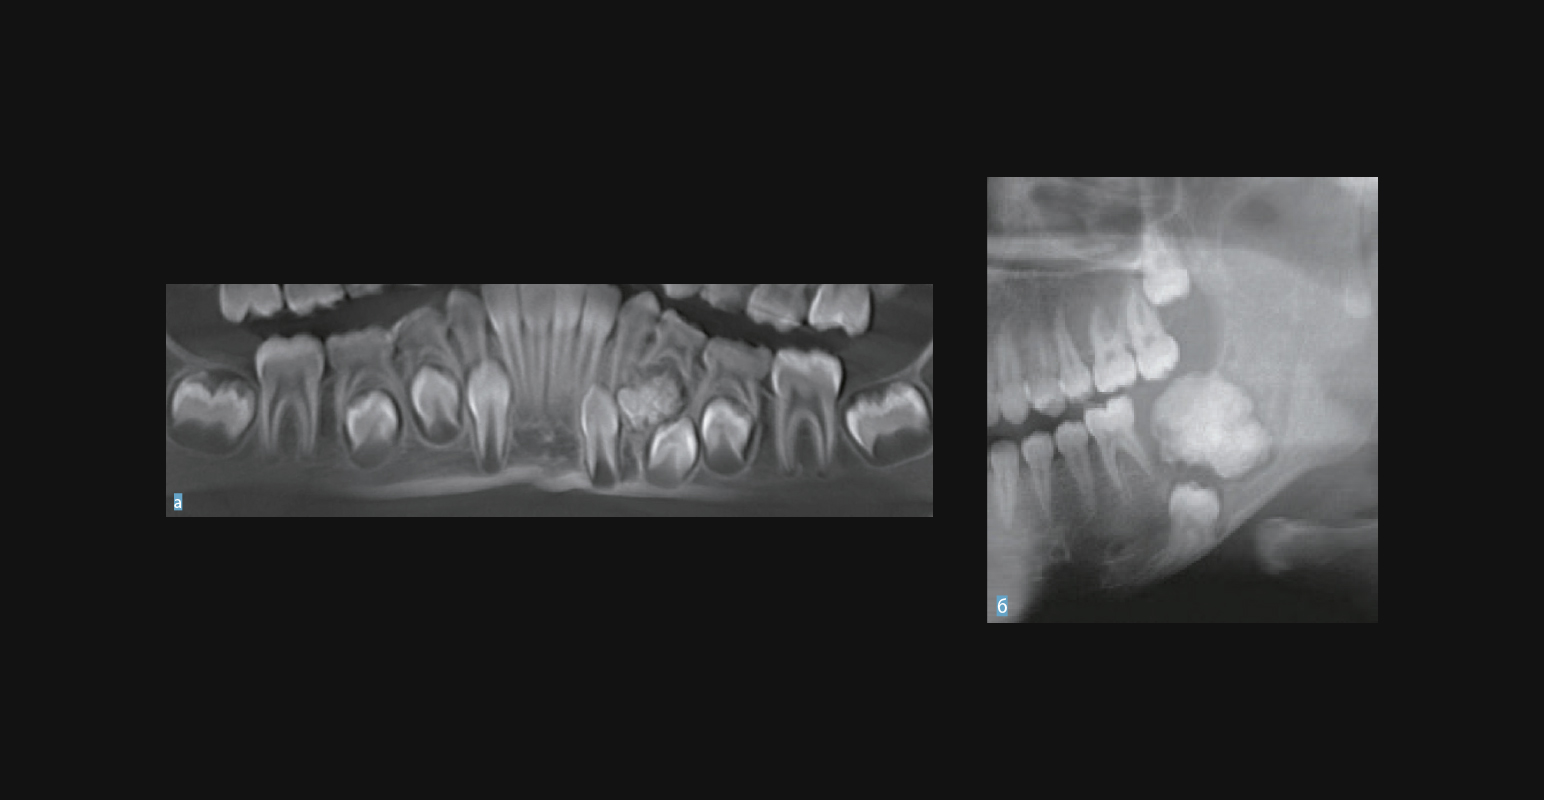

Одонтома нижней челюсти: фотографии и медицинская информация